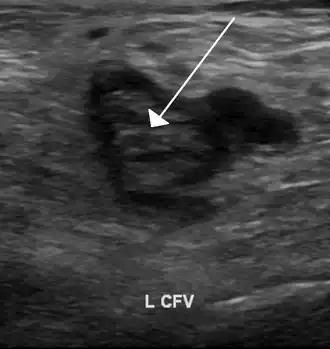

Compression ultrasonography for suspected deep vein thrombosis is the standard diagnostic method, and it is highly sensitive for detecting an initial DVT.[13] A compression ultrasound is considered positive when the vein walls of normally compressible veins do not collapse under gentle pressure.[19] Clot visualization is sometimes possible, but is not required.[82] Three compression ultrasound scanning techniques can be used, with two of the three methods requiring a second ultrasound some days later to rule out the diagnosis.[13] Whole-leg ultrasound is the option that does not require a repeat ultrasound,[13] but proximal compression ultrasound is frequently used because distal DVT is only rarely clinically significant.[9] Ultrasound methods including duplex and color flow Doppler can be used to further characterize the clot[9] and Doppler ultrasound is especially helpful in the non-compressible iliac veins.[82]

An ultrasound with a blood clot visible in the left common femoral vein. (The common femoral vein is distal to the external iliac vein.)